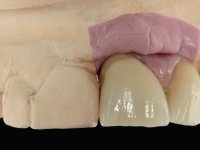

Primeira Fase

Foram feitas as extrações das raízes dos dentes 2.1 e 2.2 porque estavam a incomodar. Após 3 meses de cicatrização fez-se o exame imagiológico e estudo implantar para colocação do implante no local do 2.1.Foi colocado um implante de 4.1mm de diâmetro por 10mm de altura, colocado ao nível ósseo. Passados 2 meses após a cirurgia implantar, foi feita a segunda cirurgia para colocação de um parafuso de cicatrização. Foi feita a impressão ao implante com técnica de moldeira aberta com silicone de dupla viscosidade um mês após. No laboratório foi confecionada uma infraestrutura metálica para uma ponte de 2 elementos aparafusada ao implante. Esta infraestrutura apresentava 2 apoios palatinos para ajudar a estabilizar os dentes 1.1 e 2.3 a recuperar do traumatismo. Recuperados os dentes, os apoios poderiam ser retirados. Esta peça apresentava uma conexão interna ao implante com sistema anti-rotacional. A prova da infraestrutura foi feita em boca sendo o seu correto ajuste verificado com controle imagiológico. No revestimento da infraestrutura foi utilizada cerâmica de tonalidade coronária e gengival. Depois de verificada em boca e aprovada pelo paciente a ponte foi apertada definitivamente e o orifício de acesso obturado.